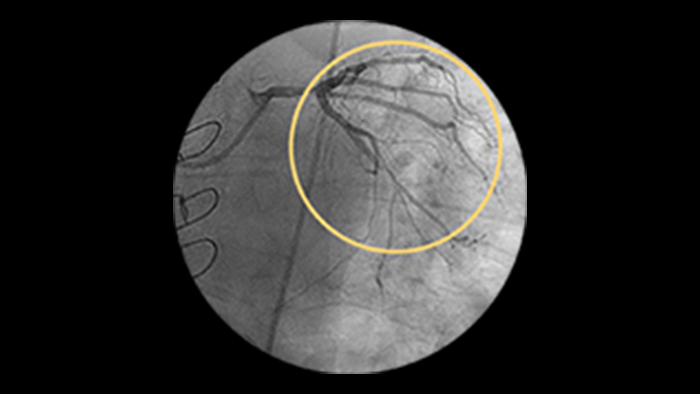

Left main disease

Significant left main CAD (greater than 50%) is found in 3-4% of all patients who undergo coronary angiography.1